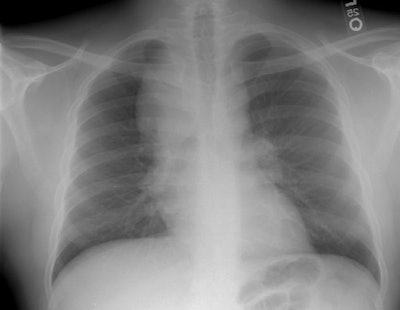

The film below was from 1997. The right paratracheal mass has enlarged markedly in comparison to the patients old film. This finding was felt to be atypical for sarcoid and a CT was performed.